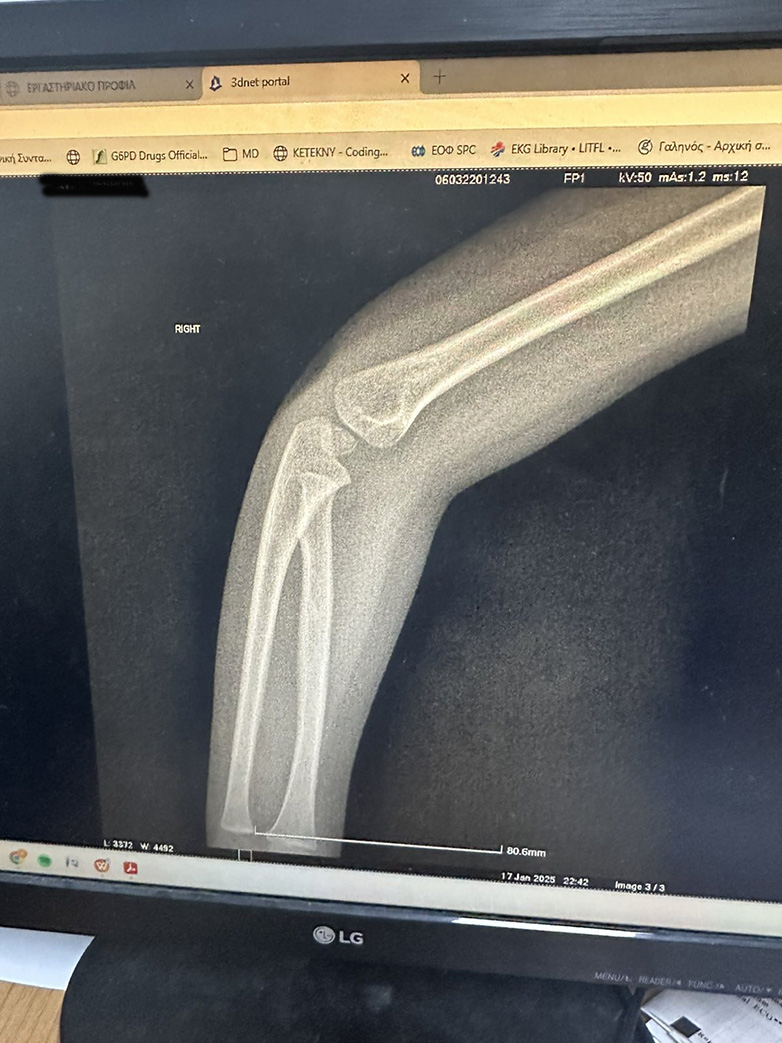

Στη συνέχεια ο πατέρας του παιδιού, μιλώντας με τον νεαρό γιατρό -που μάλλον ήταν ειδικευόμενος- όπως μας είπε, ρώτησε τι θα γίνει με το παιδί το οποίο εξακολουθούσε και πονούσε πολύ. Ο γιατρός τους έστειλε να βγάλουν ακτινογραφίες. Όντως έβγαλαν ακτινογραφίες της μικρής και στη συνέχεια ο γιατρός τις πήρε μέσω φωτογραφίας στον υπολογιστή του, αλλά επειδή ο ίδιος δεν ήταν ορθοπεδικός δεν μπορούσε να κάνει διάγνωση.

Ο πατέρας της μικρής τον ρώτησε αν έχει επιστρέψει ο ορθοπεδικός στο πόστο του λαμβάνοντας αρνητική απάντηση. Στη συνέχεια ρώτησε αν θα επιστρέψει ο γιατρός, χωρίς αυτή τη φορά να λάβει κάποια καταφατική απάντηση από τον γιατρό, που συνομιλούσε μαζί του. Αντ’αυτού, ο γιατρός είπε ότι θα στείλει τις ακτινογραφίες στο Viber στον εφημερεύοντα ορθοπεδικό, ώστε να τις δει και να του δώσει οδηγίες!

Οι ακτινογραφίες στάλθηκαν στο Viber του εφημερεύοντα ορθοπεδικού, ο οποίος μπορεί να μην ήταν στη εφημερία του στο νοσοκομείο -ως όφειλε- ήταν όμως…online. Ο εφημερεύων – και απών – ορθοπεδικός απάντησε αμέσως, όταν έλαβε τις φωτογραφίες με τις ακτινογραφίες – οι οποίες είναι αυτές που βλέπετε – και έκανε ή μάλλον καλύτερα δεν έκανε διάγνωση, απαντώντας πάντα μέσω Viber ότι δεν μπορεί από το κινητό να διακρίνει αν υπάρχει ή όχι σοβαρό πρόβλημα. Μάλιστα, συνέχισε λέγοντας ότι καλύτερα θα ήταν να φύγουν οι γονείς με το τριών ετών παιδί τους και να πάνε στην Πάτρα στο νοσοκομείο Παίδων «Καραμανδάνειο».